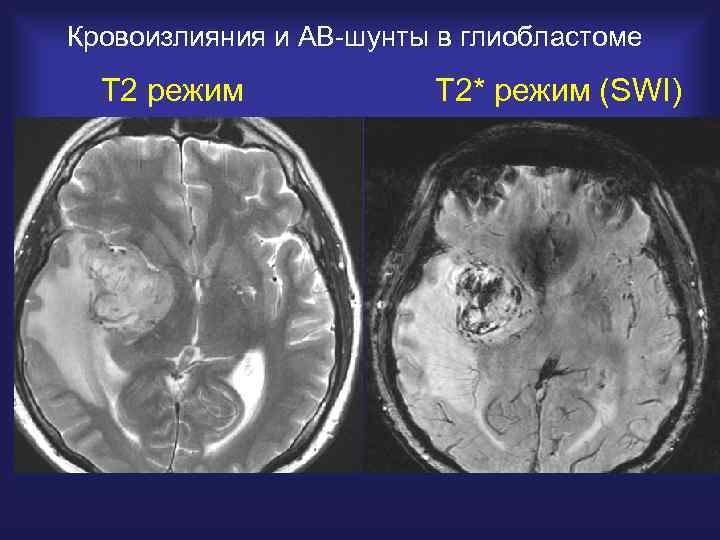

Кровоизлияния и АВ-шунты в глиобластоме Т 2 режим Т 2* режим (SWI)